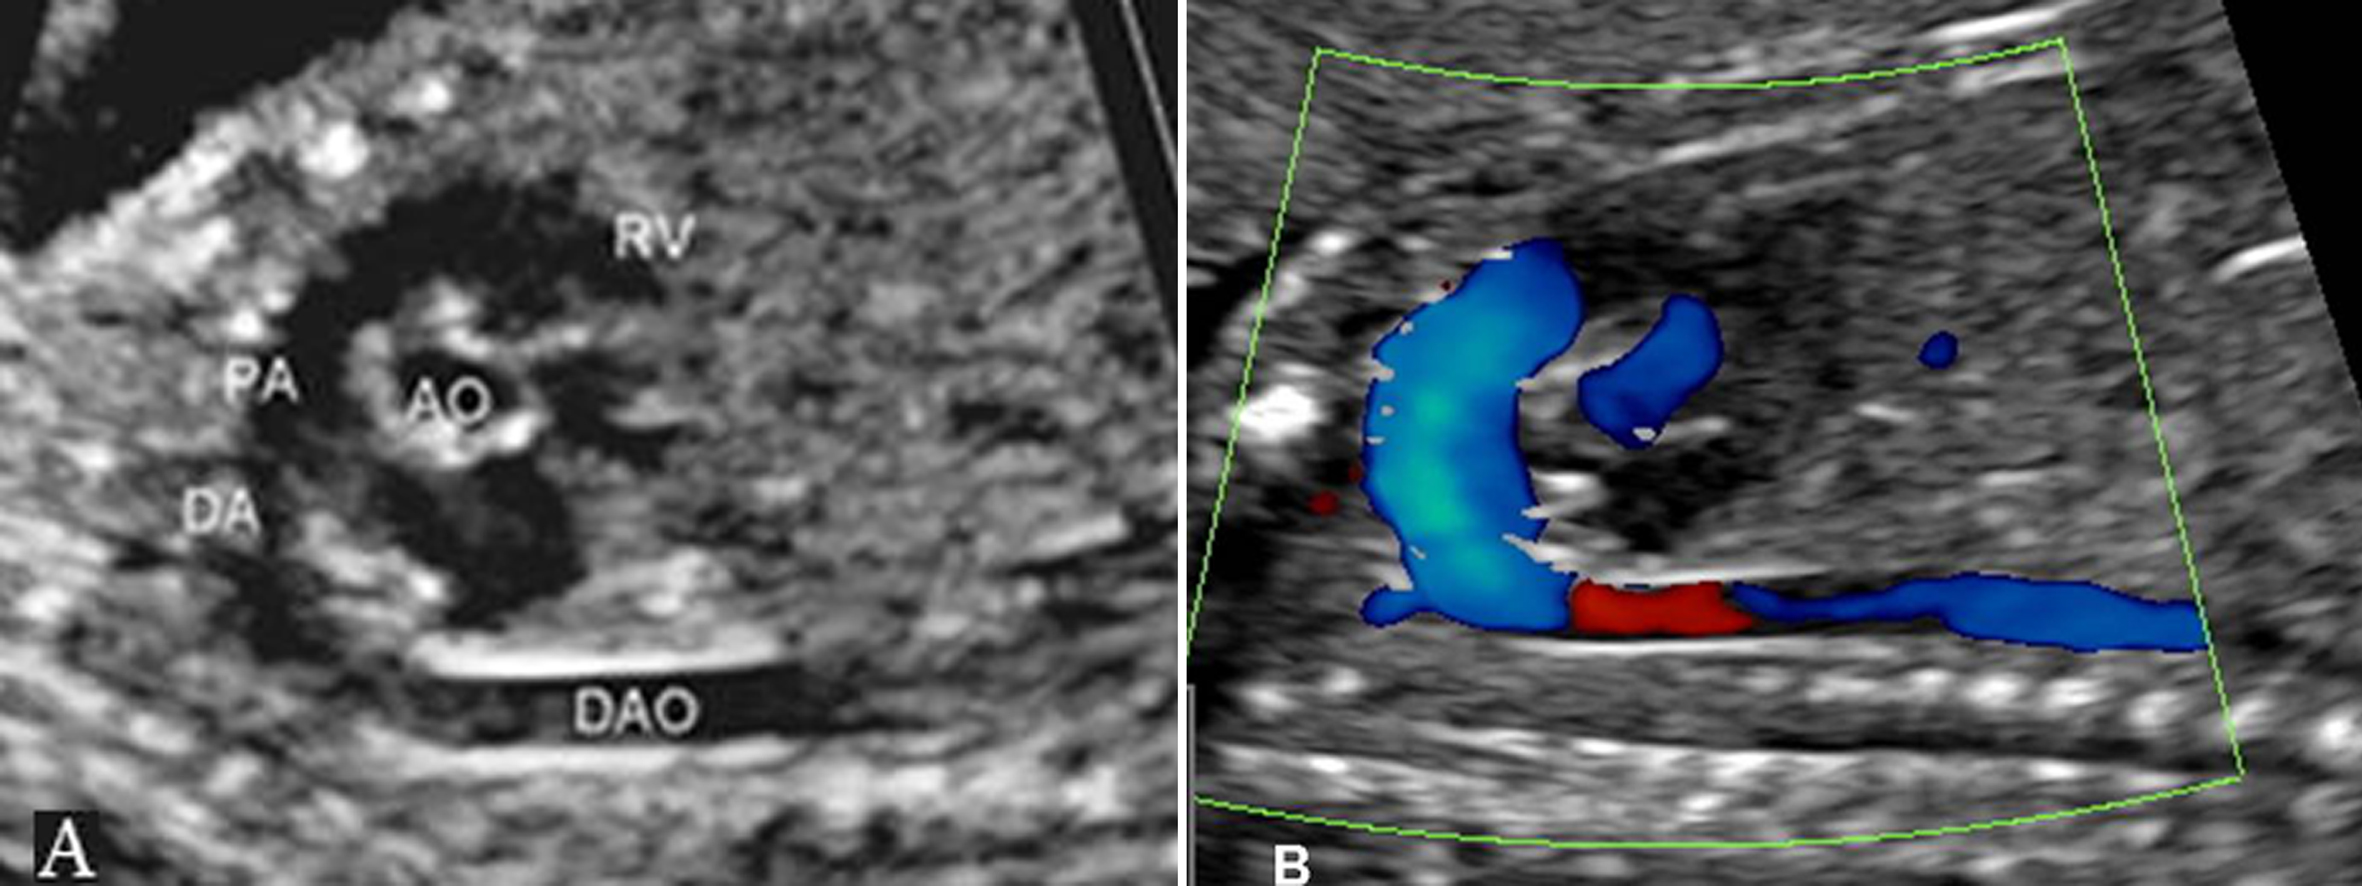

1.主动脉(AO)瓣及AO根部 多个切面都可显示AO根部和LV相连的情况,血流显示清楚。在色彩上,AO要比肺动脉(PA)鲜艳,血流速度比PA内的血流速度快,其原因可能与AO内径较细、远端血流阻力较PA的阻力小有关(图2、图3)。

图2 左室流出道切面观(A)及血流(B)

图3 主动脉(A)及肺动脉(B)血流时间流速曲线

AO的血流频谱为窄带单峰,上升支较下降支快。由于升主动脉和主动脉弓的血液主要来自胎儿的LV,在心室的舒张期可以发现血流中断,形成有空窗的基线。

2.肺动脉瓣及PA 显示相对困难,有报道认为胎儿PA的血流显示率不足一半,并且血流速度最快的部位在动脉导管处。PA的频谱显示为非对称性的三角形,上升速度大于下降速度(图3、图4)。

图4 右室流出道切面观(A)及血流(B)